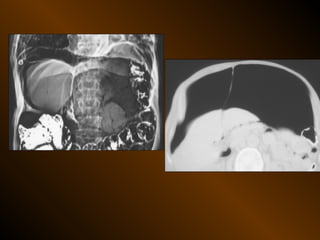

• X QUANG CẮT LỚP ĐIỆN TOÁN

• Kỹ thuật

• Chuẩn bị ?

• Cách thu thập : lát cắt, trường, ma trận

tiêm chất cản quang tĩnh mạch ?

tái tạo ?

• Ưu, khuyết điểm

• Chỉ định

• Phân tích kết quả : của sổ hiển thị

• SIÊU ÂM

– Phản âm trống, chuyển dịch

– Lượng ít

– Bản chất dịch

– Mật độ

– Vị trí

– Nguyên nhân